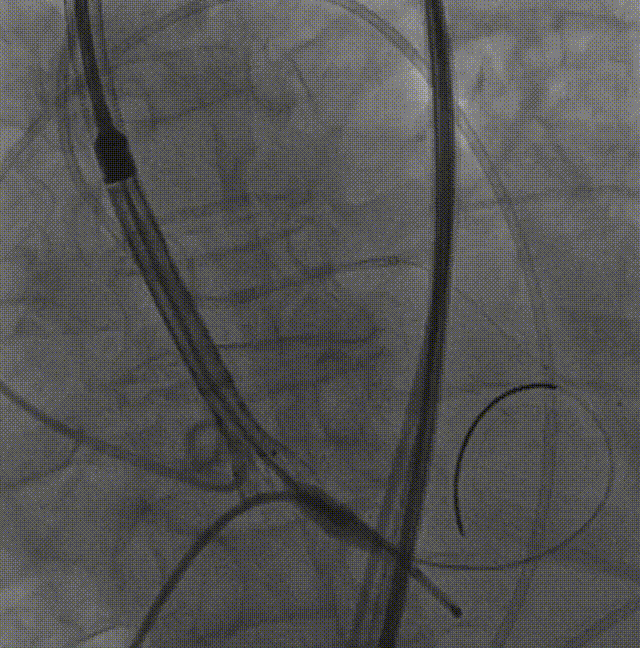

瓣膜内22mm球囊后扩张,左冠无显影

LM烟囱支架植入4.0*30mm